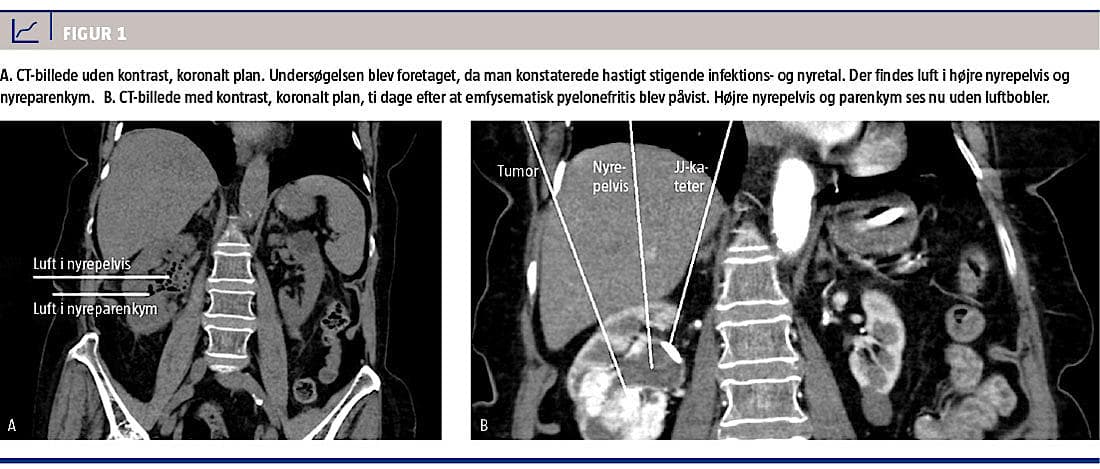

Antibiotisk behandling med cefuroxim blev iværksat på mistanke om pyelonefritis. Efter 12 timer steg leukocytniveauet til 29,8 × 109/l, CRP-niveauet til 115 mg/l og kreatininniveauet til 199 mikromol/l. Ved en akut foretaget CT af abdomen blev der påvist en højresidig obstruerende nyretumor på 60 × 40 mm med let hydronefrose, dilatation af den proksimale ureter samt EPN med luftbobler i nyrepelvis og

i nyreparenkymet (Figur 1A).

Den antibiotiske behandling blev suppleret med metronidazol og ciprofloxacin. Man forsøgte aflastning af højre nyre med nefrostomi, men det mislykkedes pga. manglende dilatation af nyrepelvis. Der blev derfor anlagt højresidigt JJ-kateter, og peroperativt sås der pusafgang fra ureterosiet. Efterfølgende faldt infektionsparametrene hastigt. Ved en kontrol-CT efter ti dage var der ingen tegn til obstruktion eller luft (Figur 1B). Ved bloddyrkning blev der påvist E. coli.